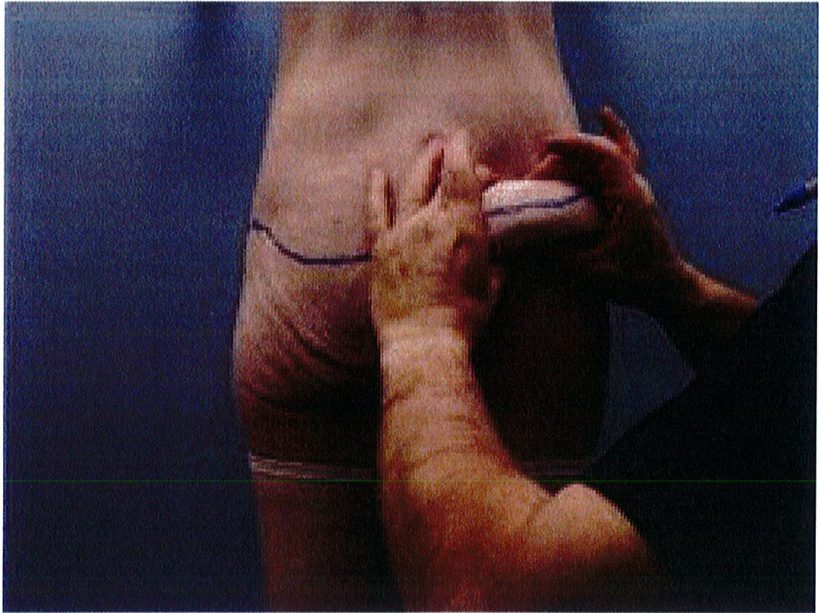

Đối tượng lý tưởng cho phẫu thuật này là bệnh nhân có vùng da và mô mềm vùng thắt lưng/mông dư thừa nhưng mông dẹt và gần như không có điểm hình chiếu. Tiêu chuẩn này có thể được xác định bằng cách dùng hai tay sờ và véo da đồng thời (Hình 2). Quy

Hình. 2. Nghiệm pháp véo da bằng hai tay được thực hiện ở đường nách trước. Để bệnh nhân nghiêng người sang bên đối diện để tránh cắt đi quá nhiều mô.